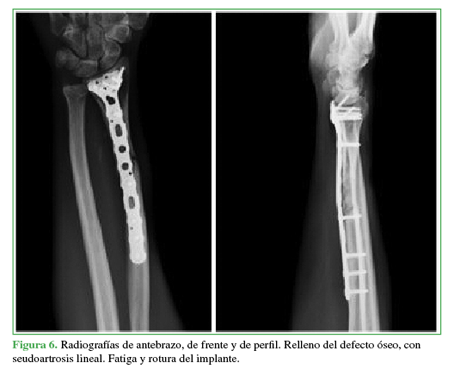

Nuevamente refirió dolor durante la carga a los ocho meses de la cirugía. En las radiografías, se observó el relleno del defecto óseo, pero con persistencia del foco de seudoartrosis lineal y fallo del implante por fatiga (Figura 6).

En consecuencia, se procedió a una nueva intervención para retirar el implante, explorar el foco, tomar muestras bacteriológicas y para la estabilización externa con yeso (Figura 7).